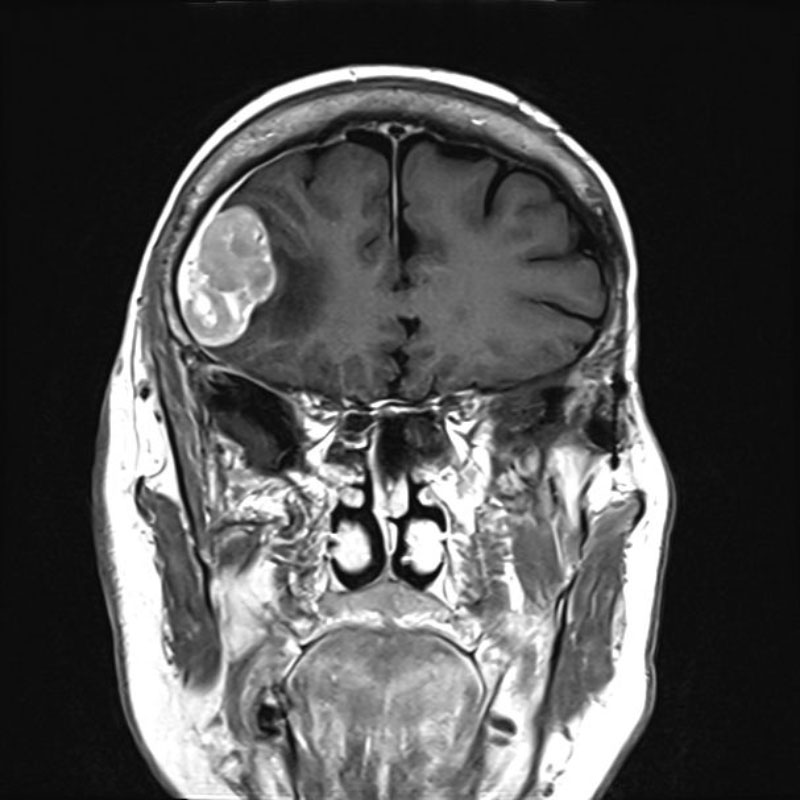

No.’25_82 手術前1

No.’25_82 手術前2